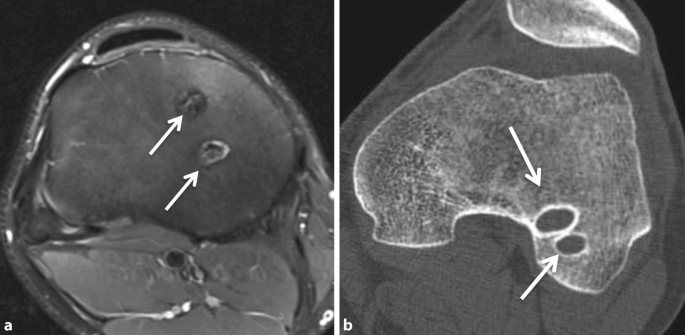

1983 wurde die Doppelbündeltechnik („double-bundle technique“) erstmals von Mott beschrieben [6]. Die Bohrung von mehreren Kanälen in die Tibia und/oder in den Femur und die Rekonstruktion beider Bündel des nativen VKB wurde über die letzten Jahrzehnte modifiziert ([7]; Abb. 4). Die Idee dahinter war, die Rotationsinstabilität, die bei 10–15 % der Patienten nach Einzelbündeltechnik entstehen kann, mit der Doppelbündeltechnik zu vermeiden. Klinische Studien zeigten allerdings, dass der klinische Benefit gegenüber der Single-Bundle-Rekonstruktion teilweise ausblieb und die markanten Knochendefekte durch die Bohrung von 2 Kanälen jeweils in der Tibia und im Femur von Nachteil sind, wenn eine Kreuzbandrevision erforderlich ist. Die Operationstechnik erfordert mehr Geschick und dauert meistens länger als die Single-Bundle-Rekonstruktion.

Abb. 4

figure 4

Sowohl in der axialen Magnetresonanztomographie (MRT; a) als auch in der Computertomographie (CT; b) sind die beiden Bohrkanäle im Tibiaplateau für die Doppelbündeltechnik erkennbar